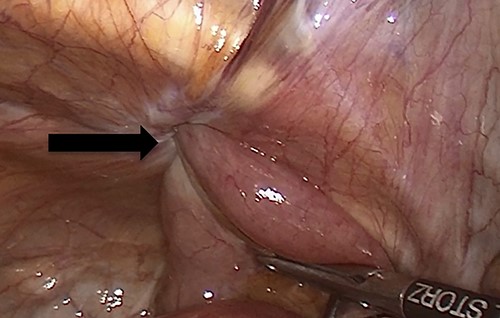

Due to the high-grade small bowel obstruction, the patient was pushed as an emergency case to the operating room. The surgery started and ended as a laparoscopic procedure with three small incisions; 12, 11 and 5 mm port sizes located supraumbilically, right and left midclavicular line relatively. Once the peritoneum was penetrated, and gas insufflated, diagnostic laparoscopy was done, and the obturator hernia with bowel content was visualized (Fig. 3), with a transitional zone at the hernia site showing a proximal dilatation and distal collapse of the small bowel. After that, reduction of the hernia content was subsequently made with no signs of gangrene or ischemia of the bowel. Then, the small bowel was run as a whole to eliminate any other transitional zones or pathology, which was unremarkable. Therefore, as there was no contamination, ischemia or perforation, a Vicryl mesh was elected and inserted as a plug into the obturator opening using a peritoneal flap and fixed (Fig. 4). Once the fixation was obtained, a ProGrip mesh was then applied to cover the whole right area (Fig. 5), which was covered by the peritoneum afterwards. The abdomen was inspected and the bowel looked healthy. Lastly, the ports were removed, the incisions were closed, the skin was clipped and then the dressing was applied.

An intraoperative figure of the right ProGrip mesh covering the whole right area.